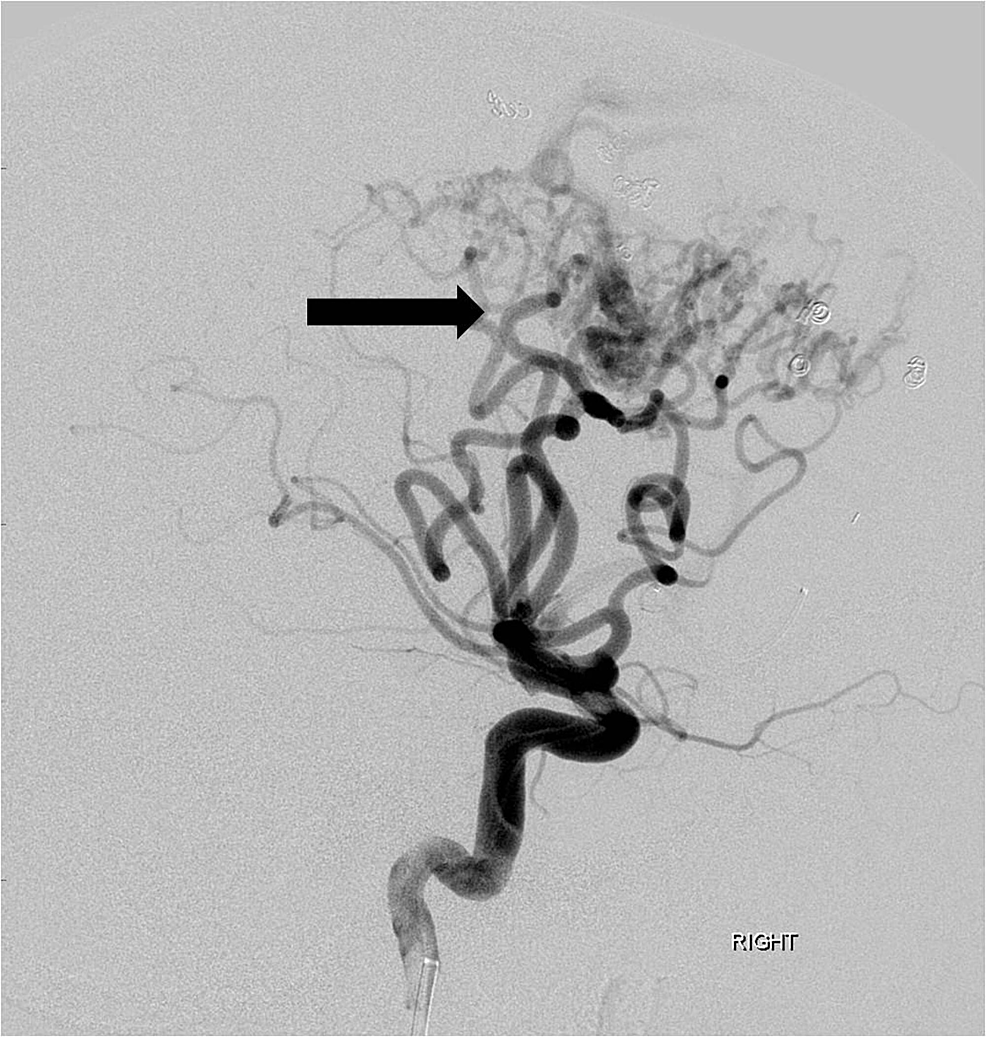

Each pedicle was treated with a combination of polyvinyl alcohol (PVA) particles (ranging in size from 250 to 500 microns), gelfoam torpedoes, and platinum coils of varying lengths and sizes. A post-embolization arteriogram demonstrated greater than 80% reduction in the overall angiographic volume of the arteriovenous malformation nidus (Figure 4).

The right middle cerebral artery feeding pedicles were not embolized due to their superficial location and ability to secure these pedicles upon initial surgical approach. The following day, the patient underwent a right frontoparietal craniotomy to resect the AVM. A subsequent postoperative head CT revealed no complications (Figure 5).